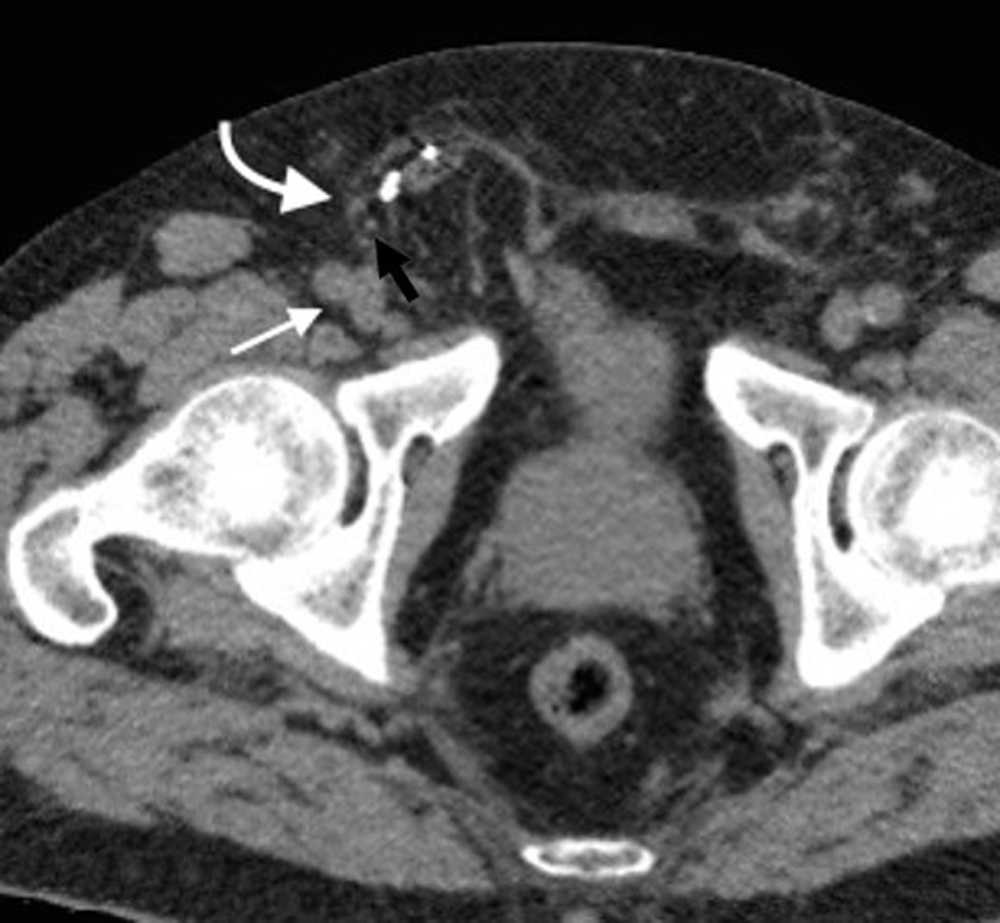

Su diagnástico clínico es difícil porque su incidencia es infrecuente, su localizaci??n profunda y tiene pocos signos o s??ntomas espec??ficos, como los relacionados con la compresi??n del nervio obturador (signo de Howship-Rombeng)10. El foramen obturador se conforma por la continuidad de los huesos isqui??ticos y p??bicos, y est?? cubierto por la membrana obturatriz, excepto en el receso anterosuperior donde es perforada por la arteria, la vena y el nervio obturador, que viajan a lo largo del t??nel de 2-3 cm formado por los m??sculos obturadores internos y externos. A trav??s de este defecto, se produce la hernia peritoneal11.

Es m??s com??n en mujeres mult??paras de edad avanzada debido a la debilidad generada en el piso p??lvico, aunque tambi??n se ve en pacientes con aumento de la presi??n abdominal y ancianos debilitados1.

Su diagn??stico espec??fico se puede hacer si en la TCMD de pelvis se visualiza el intestino herniado entre los m??sculos pect??neo y obturador externo con obstrucci??n del intestino delgado sin una causa aparente3 (fig. 4).